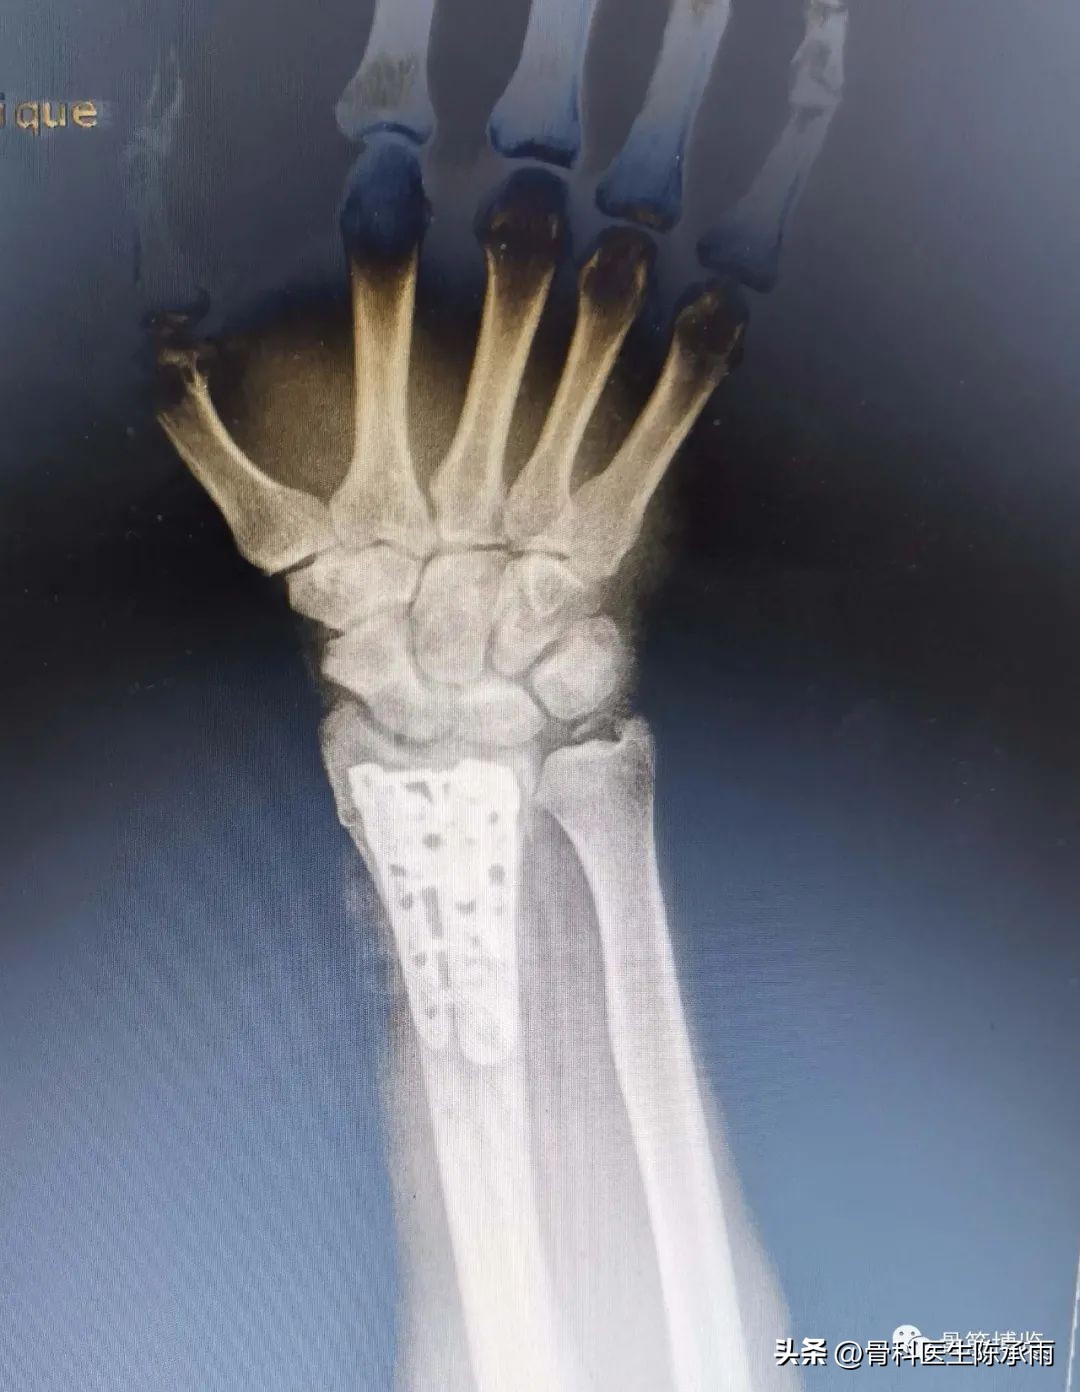

术后影像